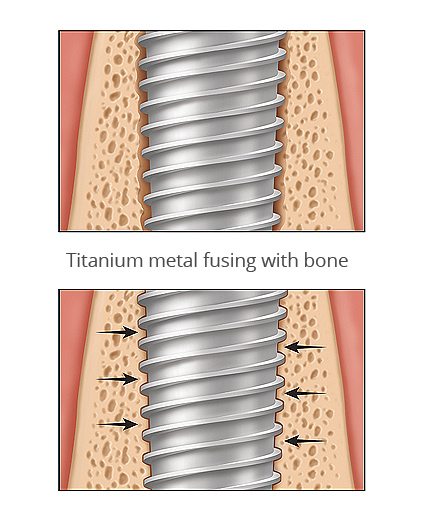

Tandheelkundige implantaten worden gebruikt om verloren tanden te vervangen. Ze zijn over het algemeen gemaakt van titanium, een metaal dat compatibel is met lichaamsweefsels en in staat is zich aan bot te binden.

Een tandheelkundig implantaat is in wezen een titaniumschroef of -cilinder, tussen 4 mm en 16 mm lang, die wordt ingebracht in een voorbereide holte in de kaak en fungeert als een vervangende wortel voor de ontbrekende tand of kies. Een speciale bevestiging, het abutment genaamd, wordt aan de bovenkant van het implantaat bevestigd en vormt de externe verbinding met de vervangende tand (kroon). Er zijn ook implantaten uit één stuk waarbij het abutment en het implantaat deel uitmaken van één stuk.

Hoe lang duurt het voordat kronen op een implantaat kunnen worden aangebracht?

Als een implantaat in de kaak is geplaatst, moet het genezen voordat de kronen kunnen worden geplaatst. Tijdens deze genezing – die twee tot zes maanden kan duren – groeien botcellen tegen het oppervlak van het implantaat waardoor een verankering ontstaat. Dit proces staat bekend als Osseo-integratie. Zodra dit proces is voltooid, is het implantaat stabiel genoeg om één of meerdere nieuwe tanden en kiezen (kronen/bruggen/suprastructuren/klikgebit) te ondersteunen.